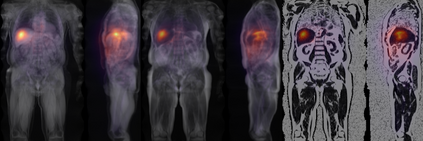

Along with rich health-related metadata, an ongoing imaging study has acquired MRI of over 40,000 male and female UK Biobank participants aged 44-82 since 2014. Phenotypes derived from these images, such as measurements of body composition, can reveal new links between genetics, cardiovascular disease, and metabolic conditions. In this retrospective study, six measurements of body composition were automatically estimated by ResNet50 neural networks for image-based regression from neck-to-knee body MRI. Despite the potential for high speed and accuracy, these networks produce no output segmentations that could indicate the reliability of individual measurements. The presented experiments therefore examine mean-variance regression and ensembling for predictive uncertainty estimation, which can quantify individual measurement errors and thereby help to identify potential outliers, anomalies, and other failure cases automatically. In 10-fold cross-validation on data of about 8,500 subjects, mean-variance regression and ensembling showed complementary benefits, reducing the mean absolute error across all predictions by 12%. Both improved the calibration of uncertainties and their ability to identify high prediction errors. With intra-class correlation coefficients (ICC) above 0.97, all targets except the liver fat content yielded relative measurement errors below 5%. Testing on another 1,000 subjects showed consistent performance, and the method was finally deployed for inference to 30,000 subjects with missing reference values. The results indicate that deep regression ensembles could ultimately provide automated, uncertainty-aware measurements of body composition for more than 120,000 UK Biobank neck-to-knee body MRI that are to be acquired within the coming years.